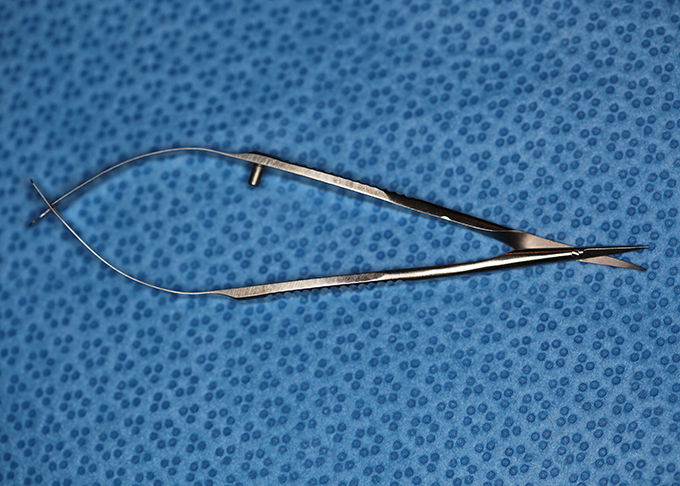

Needleholder, micro titanium micra curved

Needle driver

Catalog: Micra N303W

Typical Use(s): Placing fine suture

Needleholder, micro titanium micra curved (Enlarged)

Needle driver

Catalog: Micra N303W

Typical Use(s): Placing fine suture